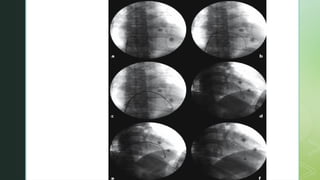

 The pigtail is removed after confirmation of tip of preformed sheath being

directed towards the mid portion of the IVS.

 Performed sheath position can be confirmed by connecting pressure line to

record RV pressure.

 On fluoroscopy, it should lie across the patients spine and is usually directed

inferiorly.

 Further confirmation can be done in RAO 30 and LAO 60 whether catheter is

on the ventricular side and facing towards the septum.

 Pigtail is then removed and 104 cm long bioptome is introduced in the

preshaped sheath.

 Contact with the IVS is confirmed by PVC.

 Bioptome is withdrawn 1-2 cm, jaws are opened and advanced slowly to

engage the septum.

 The biopsy head is slowly closed to encapsulate the endomyocardial

specimen.

 Due to trabeculated nature of the surface, gentle forward pressure has to be

maintained while jaws are closed.